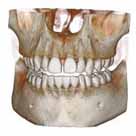

volumeをXYZ方向にそれぞれ512分割しておりこのときのスライスピッチは標準モード撮影で147㎛、高解像度モード撮影(ハイレゾ)で101㎛です。 3D画像はリアルタイムで自由に動かすことができるので骨の形態や奥行きを容易に把握できます。 さらにウィンドウレベルを操作することでさまざまな画像を簡単に得ることができます。 またインプラント治療においては下顎管やオトガイ孔、上顎洞下壁までの距離を正確に測定できるので術中も安全に治療をおこなうことができます。 |

前頭断での術前シュミレーション

(直径5㎜被覆長8㎜での想定)

矢状断での術前シュミレーション

(約3㎜程度のソケットリフトが必要)